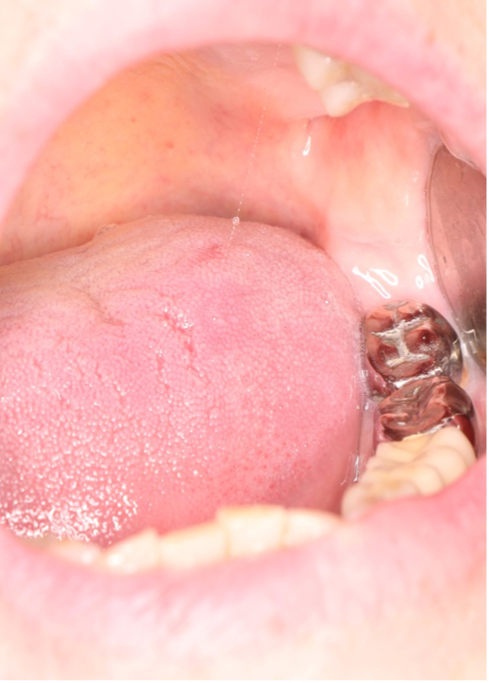

Клинический случай десквамативного глоссита на фоне гальваноза, участки десквамации визуализируются в области цельнолитых коронок с шероховатой окклюзионной поверхностью

Жжение постоянно, усиливается к вечеру. Пациенты часто связывают появление жжения после повторного ортопедического лечения или после 10–15 лет пользования металлическими протезами Рис.30.